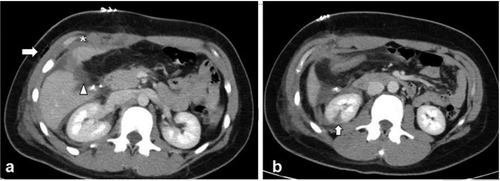

Scans reveal differences in lesion locations, mucoid impaction, and pleural effusion.